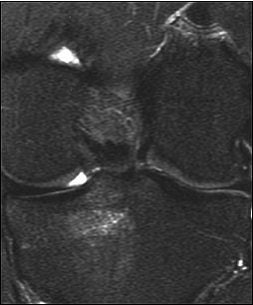

| A 31-year-old man with fast resolution of bone bruise, reticular lesion type. Coronal T2-weighted fast-suppressed images (TR/TE, 12/3,700; fat saturation; section thickness, 3 mm; field-of-view, 180 x 135 mm; matrix, 385 x 224) show fast resolution of bone bruise from baseline (above), to three-week follow-up (middle), and at nine-week follow-up (below). |